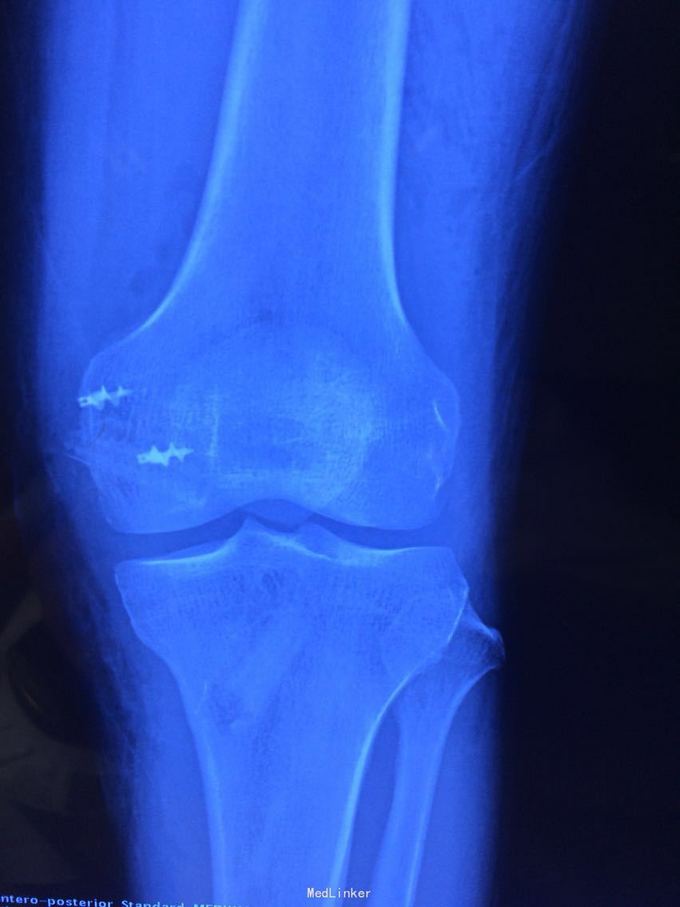

诊断:膝关节多发韧带损伤,后交叉韧带、内侧副韧带 处理:给予关节镜下后交叉韧带重建,小切口修补内侧副韧带,取自体半腱股薄肌腱

后交叉韧带和内侧副韧带也有协同作用,后交叉韧带相比前交叉韧带术后容易出现松弛,故内侧副韧带也一期给予修补,后交叉韧带也可以选择inlay方法,但首次重建建议全镜下。